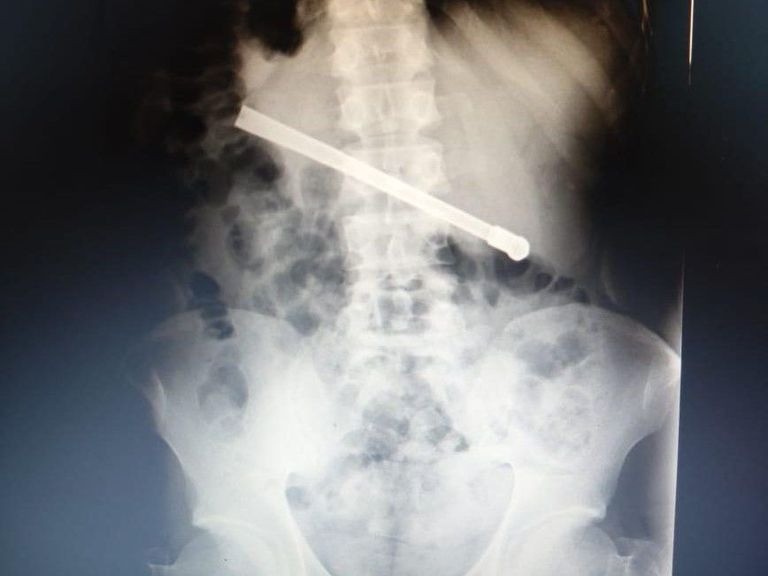

Un preso de 35 años alojado en el Complejo Penitenciario de Rosario debió ser intervenido quirúrgicamente en el Hospital Eva Perón luego de tragarse una bombilla de mate que quedó alojada en su tórax.

El hombre, condenado por abuso sexual, comenzó a sufrir intensos dolores estomacales mientras se encontraba en la Unidad Penitenciaria ubicada en 27 de Febrero al 7800. Ante la sintomatología, le realizaron una radiografía que confirmó la presencia del objeto extraño atravesando la cavidad torácica.